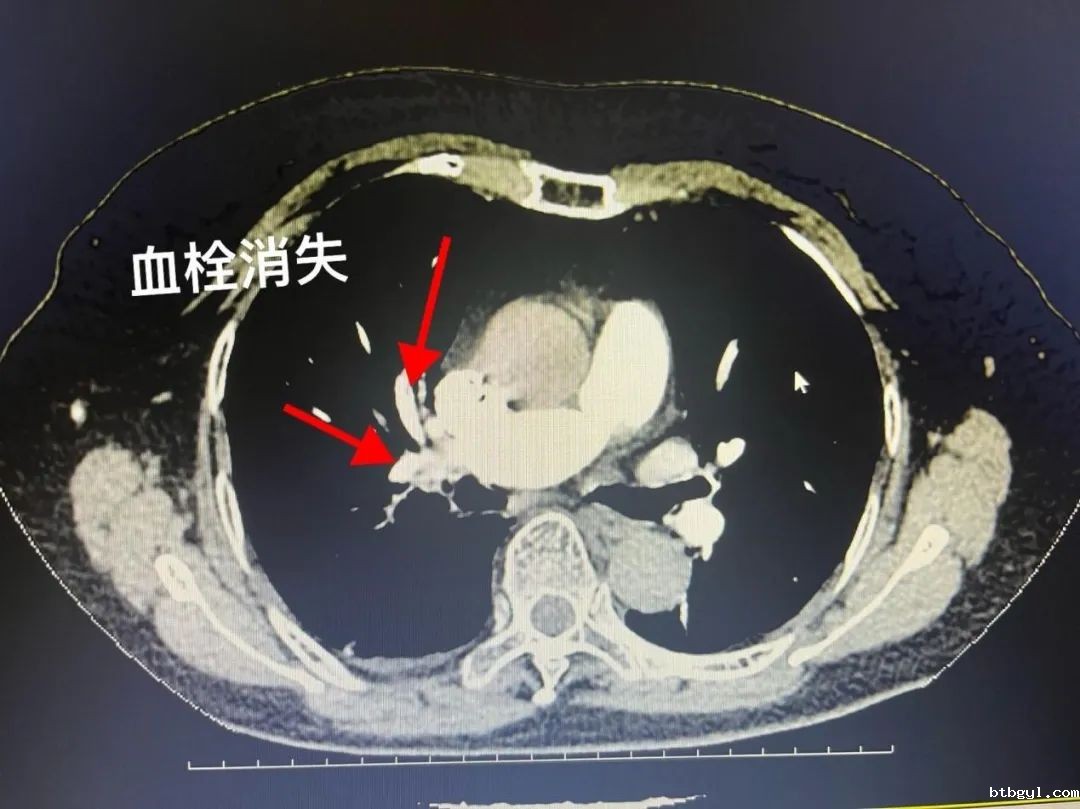

医生向患者家属沟通该疾病的潜在风险及治疗方案后,患者家属立即选择行下腔静脉滤器置入+肺动脉栓塞取栓溶栓术。 术后继续行标准抗凝治疗,抗凝5天后复查CTPT。 经过血管外科医护的精心治疗,何婆婆顺利出院了,术后继续抗凝3-6月,门诊随访既可。